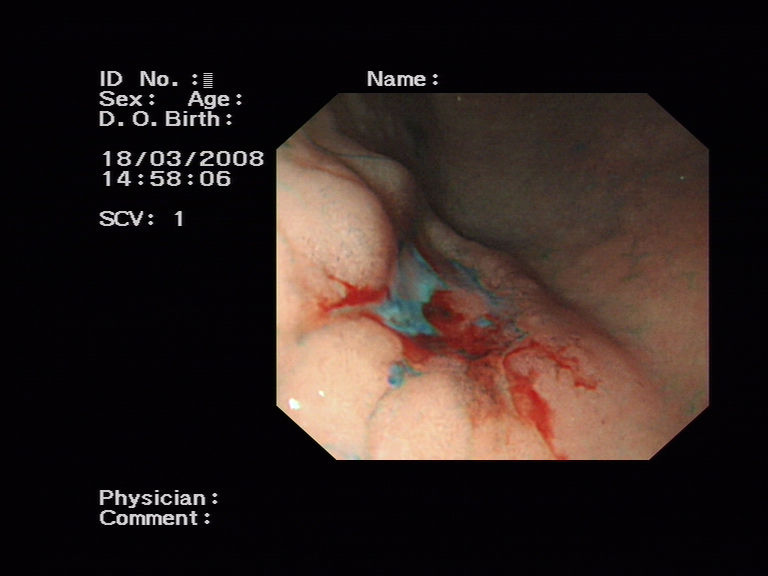

宜宾市第二人民医院 图文